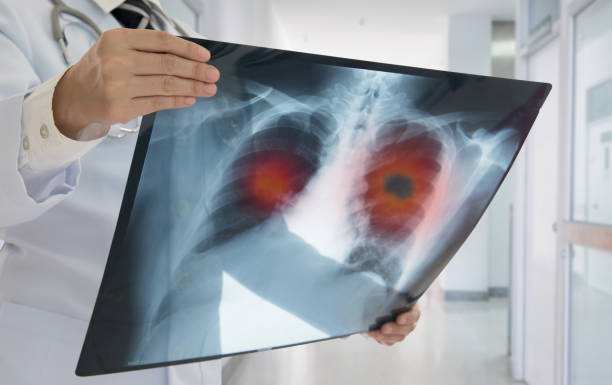

폐암은 폐에서 생기는 악성 종양으로, 결절이라고도 불립니다.

이러한 결절은 폐 내에 작은 덩어리 혹은 종양으로 나타날 수 있으며, 그 중에서도 양성과 악성 종양이 구분됩니다.

악성 종양은 일반적으로 암이라고 알려져 있으며, 폐암이라고도 불립니다.

또한, 정기적인 건강 검진, 특히 엑스레이 등의 폐 검사를 받는 것도 중요합니다. 호흡기 증상이나 다른 이상 증상이 있을 경우, 빨리 의료 전문가와 상담하여 필요한 검사를 받는 것이 생명을 지킬 수 있는 선택일 수 있습니다.